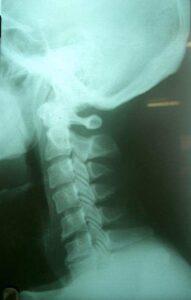

어깨만의 문제라면 목의 위치에 상관없이 모두 다 잘 올라가지 않아야 하지만, 목의 위치에 따라 어깨를 들어 올릴 때의 통증이나 들어 올리는 정도가 변하면 척추에 기인한 어깨 통증으로 판단할 수 있고 추나요법이 필요합니다.